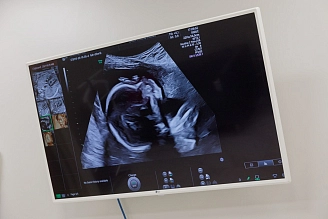

Ультразвуковой скрининг при беременности позволяет оценить развитие плода, состояние плаценты и околоплодных вод, уточнить срок гестации и положение ребенка. Плановые скрининги выполняют в установленные периоды, но при необходимости врач может рекомендовать дополнительные исследования для уточнения данных.

У детей ультразвуковое исследование используют для контроля развития органов, диагностики врожденных особенностей и динамического наблюдения за состоянием. Для новорожденных применяются датчики меньшего размера и повышенной частоты, что позволяет получать четкое изображение при коротком времени процедуры.

Это делает УЗИ оптимальным инструментом наблюдения за состоянием беременных женщин и детей без риска для здоровья.